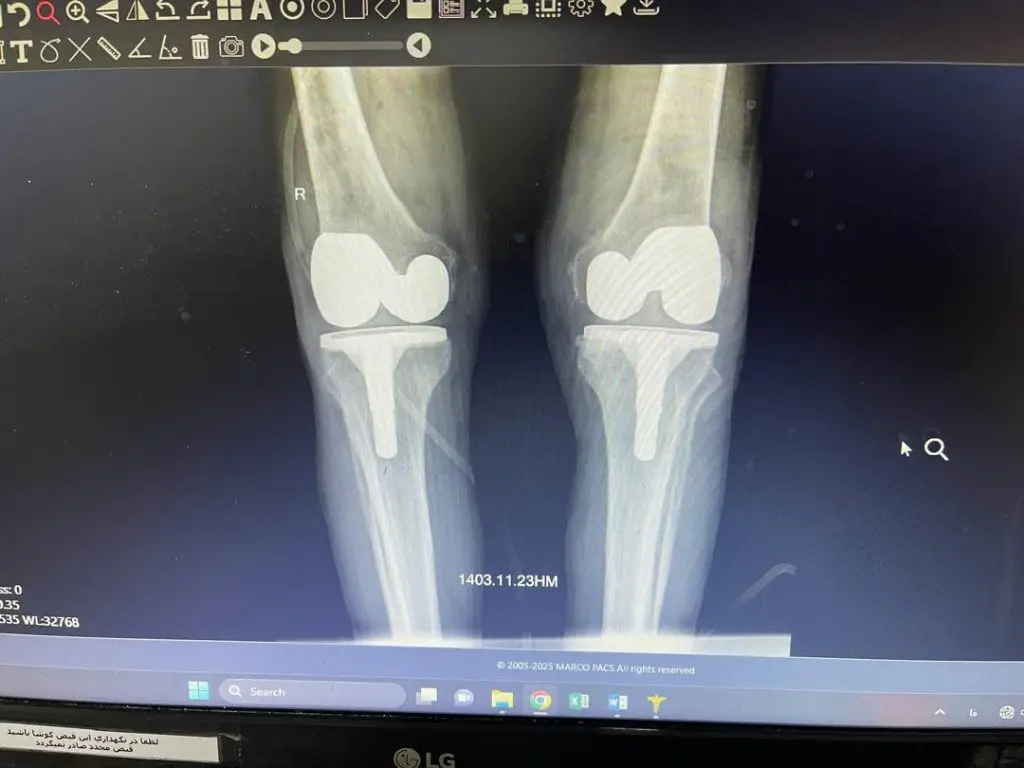

تعویض مفصل زانو یا Total Knee Replacement (TKR) که با نام آرتروپلاستی زانو نیز شناخته میشود، یکی از موفقترین جراحیهای ارتوپدی در سراسر دنیاست.

در این عمل، بخشهای آسیبدیده از مفصل زانو (غضروف و استخوانهای ساییدهشده) با قطعات مصنوعی از جنس فلز، سرامیک یا پلاستیکهای مخصوص جایگزین میشوند.

- اصلاح تغییر شکل: رفع دفورمیتیهای زانو مثل پای پرانتزی یا ضربدری.

- دوام بالا: مفاصل مصنوعی امروزی بین ۱۵ تا ۲۰ سال عمر مفید دارند و در بسیاری موارد بیشتر نیز دوام میآورند.